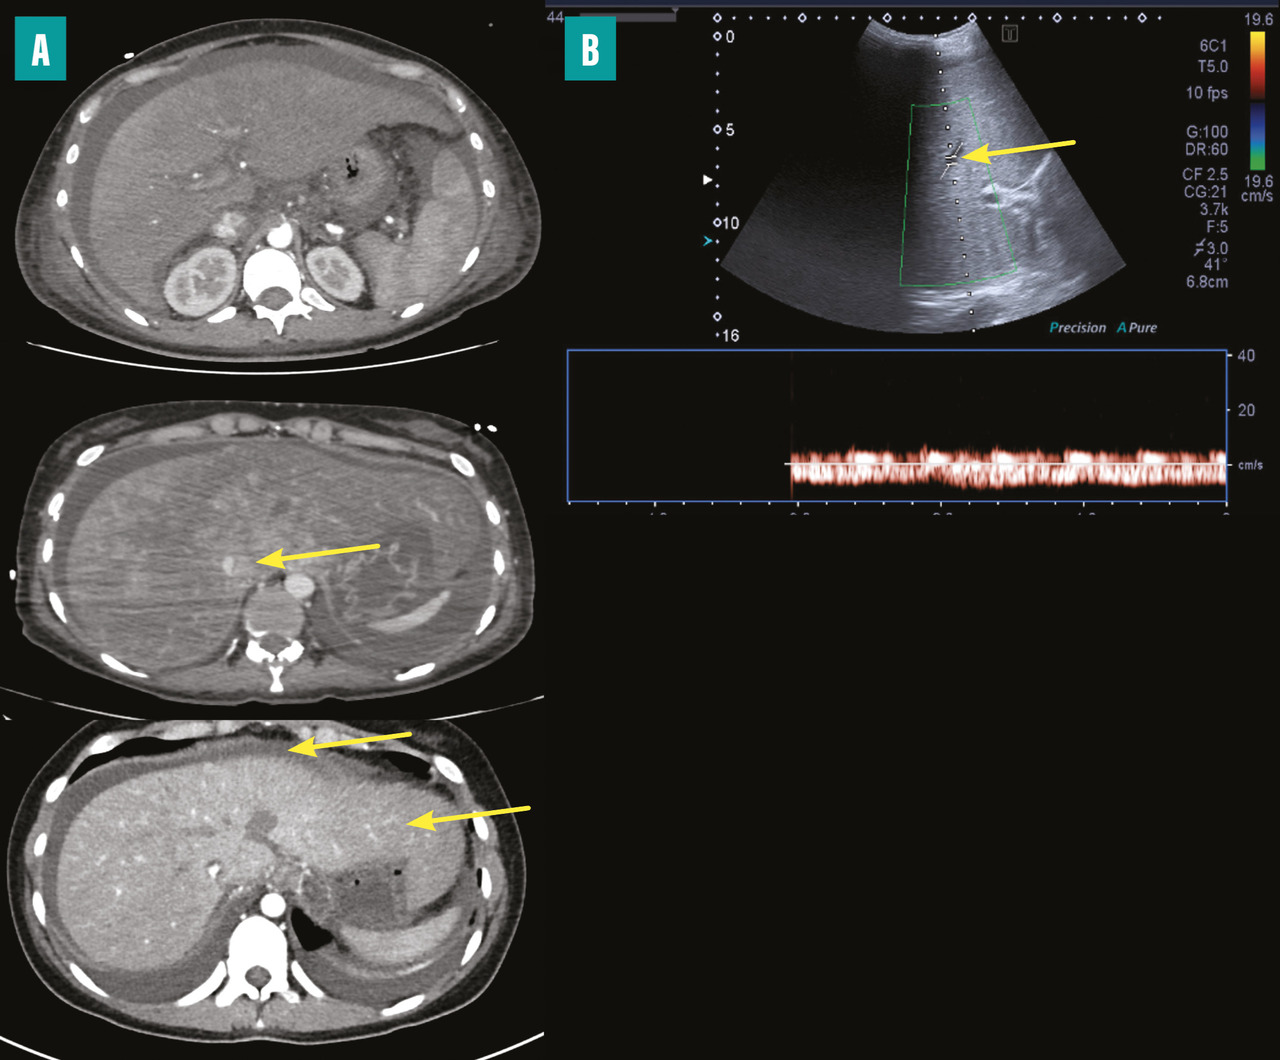

Dans presque tous les cas, les méthodes d’imagerie non invasives révèlent une obstruction des voies de drainage veineux hépatique. L’obstruction est confirmée par un flux sanguin stagnant ou inversé, la présence de matériel solide dans la veine, une obstruction avec dilatation en amont ou une transformation des veines en un cordon fibreux sans flux (fig. 2). Des signes indirects d’obstruction tels qu’une hépatomégalie congestive, des collatérales veineuses interhépatiques, une atrophie des segments atteints et une hypertrophie des segments non atteints ainsi que des signes d’hypertension portale peuvent également être observés.2 L’échographie abdominale couplée à un Doppler reste la méthode de référence pour le diagnostic, avec une sensibilité supérieure à 75  %, à condition que l’opérateur soit expérimenté et informé de cette hypothèse diagnostique.3 Les méthodes d’imagerie en coupes avec injection de produit de contraste (tomodensitométrie et imagerie par résonance magnétique) sont utiles pour caractériser la circulation collatérale inter- sus-hépatique, la veine cave inférieure, le tronc porte et les nodules, et pour rechercher des signes de SBC secondaire. Ces techniques peuvent révéler des images en toile d’araignée remplaçant l’aspect normal des veines hépatiques près de l’ostium, des images hyperdenses aux emplacements des veines hépatiques et des troubles de la perfusion hépatique (aspect en «  mosaïque  » dû à la congestion et à la dilatation sinusoïdale). Un rehaussement du segment I du foie est également visible lors de l’acquisition précoce après injection de produit de contraste, qui permet aussi la détection de nodules hépatiques.8